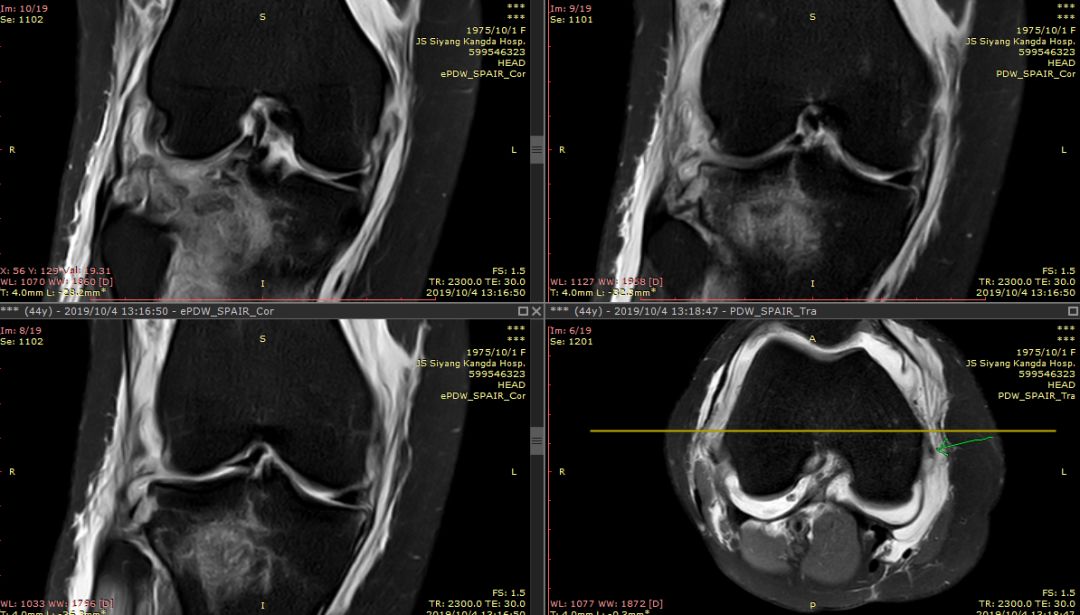

女44岁,外伤

前交叉韧带“消失”

外侧半月板后角“消失”

下图横断面的标线标记的是左下图,为外侧半月板的桶柄样撕裂移位

下图标记的是外侧半月板的撕裂

下图示外侧副韧带损伤 腘肌腱损伤 髂胫束连续

内侧副韧带损伤

膝后肌群损伤